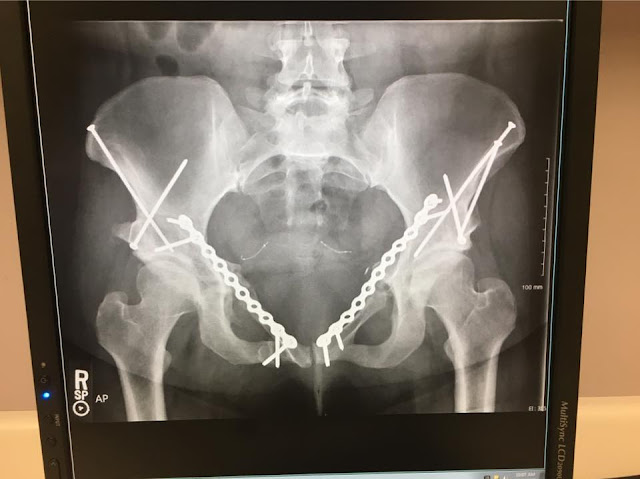

4th Hip/Pelvic Surgery

I had a 4th hip/pelvic surgery on April 11th, 2018 to replace the lower pelvic screws, as they were causing me a lot of pain in my pelvic area. The x-ray on the right was pre-surgery, and the photo on the left was the day of surgery. The screws are significantly shorter now, and I can't feel them anymore (thank goodness). The surgery was successful, and I had a minimal recovery time. They did another c-section-like cut (just like in the surgery in October 2017), this cut was only about 2 inches long. I have very minimal pain, and I was back to my normal activities almost immediately. I had my 6-week post-op appointment back on May 24th, and all was looking well. Dr. JS also noticed more signs of healing where they did my left hip bone graft back in October, so great news!

(X-RAY TAKEN 12/06/2017)

I had my Pelvic/Hip Surgery on October 27th, 2017 - conducted by two surgeons (Dr. JS & Dr. CB). If I remember right - the surgery took about 4-5 hours to complete. This surgery was to correct a few non-unions due to my right and left hip PAO surgeries & stress/fall. They did a bone graft to fill two larger non-unions, then put plates going across on the right and the left. Then, a screw into the non-unions on my lower pelvic bone. I am not a doctor, obviously, so I am unsure of bone names.

I met with Dr. JS again yesterday. The x-ray indicated that that the bone graft on my left side isn't healing as expected. On a positive note, the right one is! I am also still feeling screws in my pelvic bone, and they are causing me quite a bit of discomfort! Dr. JS conducted a Pelvic Exam, with a nurse present, so he could better understand what I was feeling & where. Dr. JS is going to consult with the pelvic doctor (Dr. CB). He stated that they are going to discuss the next steps, and contact me by the end of the week.